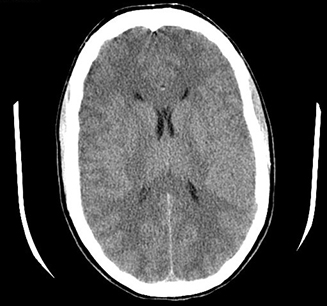

Get Medication For Brain Swelling Images. It's also usually more difficult to treat. Hi, i have a 75 year old female friend who suffered crushed optic nerves 20 years ago from brain swelling.

Rebecca runge in such cases, miller and josephson said, the treatment is for the patient to stop taking the particular medication. The patient may feel disoriented and confused, or suffer from temporary loss of vision or consciousness. Medical and neurological complications determine the final functional outcome, community reintegration as well as employment potential after a traumatic brain injury. Traumatic brain injuries may be emergencies.